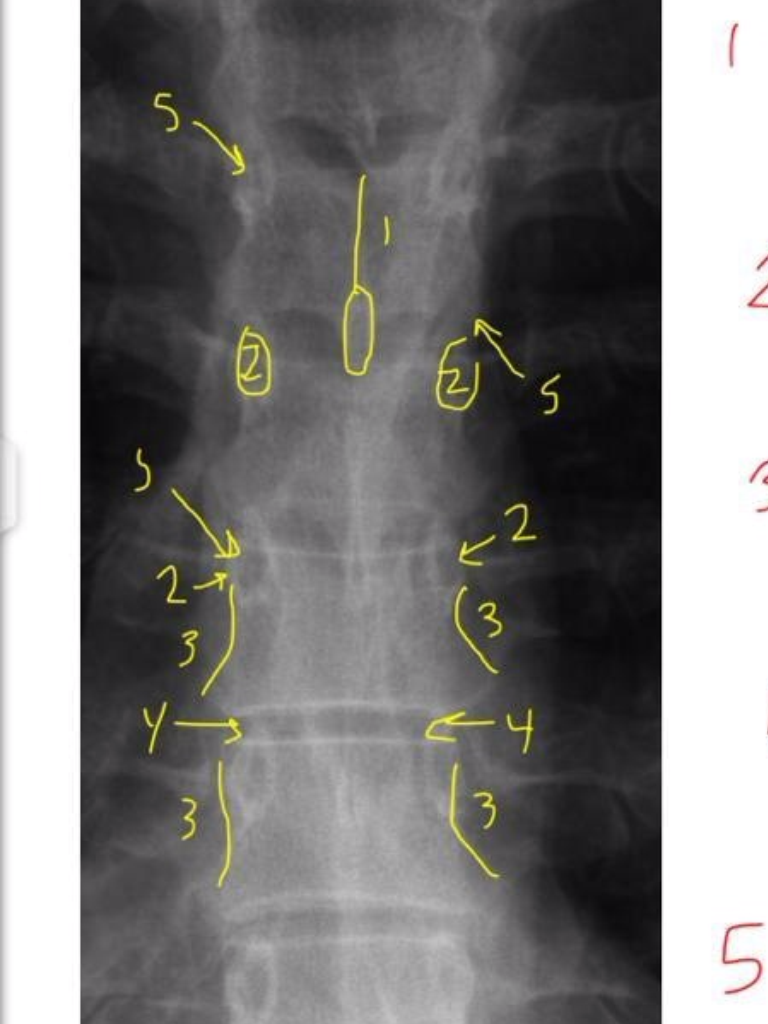

20

Q

2

A

Pedicle Shadows

21

3

vertebral waist

(biconcave aspect of body)

22

4

Disc Spaces

(not disc itself)

23

5

Endplate Tips

(vertebral body)

24

1

Junction of Laminae

(tip of spinous)

25

Uncinate Processes

26

Inferior Aspects of Vertebral Bodies